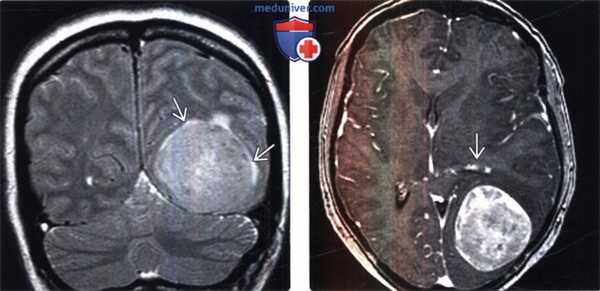

(Слева) МРТ, Т2-ВИ, корональный срез: у мужчины 47 лет определяется внемозговое образование однородной структуры с четкими контурами с минимальным отеком.

(Справа) МРТ, постконтрастное Т1 -ВИ, аксиальный срез: у этого же пациента визуализируется интенсивное относительно однородное контрастное усиление. Обратите внимание на компрессию треугольника левого бокового желудочка. Несмотря на отсутствие агрессивных рентгенологических признаков при хирургической резекции и гистологическом исследовании была диагностирована злокачественная Менингиома grade III. Для окончательного установления гистологического типа и степени злокачественности менингиомы необходима биопсия.

(Слева) МРТ, высокоразрешающее Т2-ВИ, аксиальный срез: у этого же пациента хорошо визуализируется гипоинтенсивное объемное образование с кистозными компонентами и четкими контурами. Гиподенсность указывает на высокое содержание клеточного матрикса в опухоли.

(Справа) МРТ, постконтрастное Т1-ВИ SPGR, корональный срез: контрастное усиление солидных компонентов опухоли. Было выполнено хирургическое удаление, был поставлен гистологический диагноз смеси светлоклеточного (grade II) и склерозирующего вариантов менингиомы.